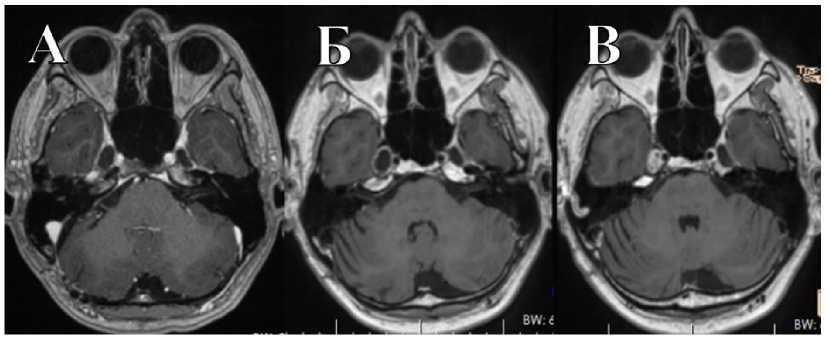

В НМИЦ нейрохирургии им. ак. Н.Н. Бурденко обратился пациент О., 33 лет. Развитие заболевания протекало в течение года в виде онемения в правой половине лица и болью в области внутреннего угла глаза. По данным МРТ, выявлена внемозговая опухоль средней и задней черепных ямок справа, накапливающая контрастное вещество, размеры узла в СЧЯ 1,2 × 1,25 × 1,4 см, в ЗЧЯ — 2,16 × 1,9 × 1,56 см (рис. 4). Объем опухоли в СЧЯ — 2,37 см3, в ЗЧЯ — 3,85 см3. При объективном обследовании перед операцией выявлены нарушения функции тройничного нерва справа в виде снижения роговичного рефлекса, а также горизонтальный нистагм.

Рис. 4. МРТ пациента О. до операции. Внемозговая опухоль СЧЯ и ЗЧЯ, накапливающая контрастное вещество

Fig. 4. MRI of patient O. before surgery. Extracerebral tumor of MCF and PCF with contrast enhancement